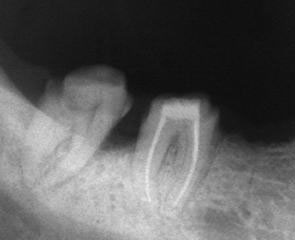

Ако при диагностична рентгенография се установи, че даден канал не е запълнен до физиологичното стеснение, е необходимо да се проведе повторно ендодонтско лечение.

В някои случаи недобре запълненият коренов канал е показание дори за отстраняване на протезни конструкции (корони и мостове) в които е включен съответният зъб.